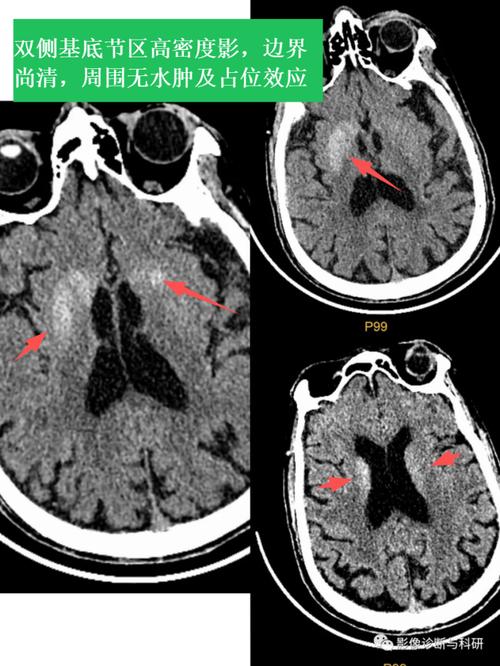

- 表现:典型病例位于基底节、丘脑或脑干,通常不累及皮层,增强扫描可能无强化,或者仅有轻微的斑片状强化。